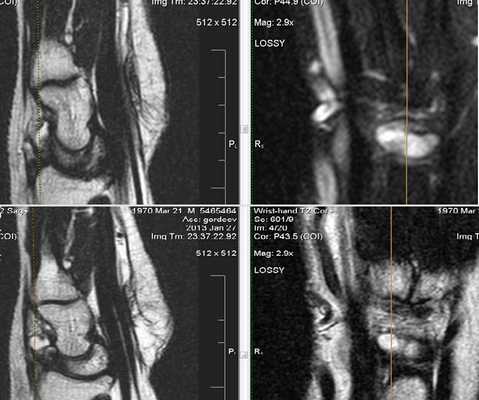

Клинически: Острая боль. В анамнезе нет травмы или чрезмерной нагрузки. Увеличение диаметра и повышение МР-сигнала в проекции сухожилия разгибателя.

Кистозное образование в проекции тыльных межзапястной и лучезапястной связок; незначительный синовит.

Ревматоидный артрит. Субхондральные эрозии, гипертрофия синовиальной оболочки.

Ревматоидный артрит. Анкилозирование костей запястья, деструкция эпифизов лучевой и локтевой костей.